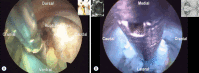

Surgical treatment of the degenerative disc disease has evolved from traditional open spine surgery to minimally invasive spine surgery including endoscopic spine surgery. Constant improvement in the imaging modality especially with introduction of the magnetic resonance imaging, it is possible to identify culprit degenerated disc segment and again with the discography it is possible to diagnose the pain generator and pathological degenerated disc very precisely and its treatment with minimally invasive approach. With improvements in the optics, high resolution camera, light source, high speed burr, irrigation pump etc, minimally invasive spine surgeries can be performed with various endoscopic techniques for lumbar, cervical and thoracic regions. Advantages of endoscopic spine surgeries are less tissue dissection and muscle trauma, reduced blood loss, less damage to the epidural blood supply and consequent epidural fibrosis and scarring, reduced hospital stay, early functional recovery and improvement in the quality of life & better cosmesis. With precise indication, proper diagnosis and good training, the endoscopic spine surgery can give equally good result as open spine surgery. Initially, endoscopic technique was restricted to the lumbar region but now it also can be used for cervical and thoracic disc herniations. Previously endoscopy was used for disc herniations which were contained without migration but now days it is used for highly up and down migrated disc herniations as well. Use of endoscopic technique in lumbar region was restricted to disc herniations but gradually it is also used for spinal canal stenosis and endoscopic assisted fusion surgeries. Endoscopic spine surgery can play important role in the treatment of adolescent disc herniations especially for the persons who engage in the competitive sports and the athletes where less tissue trauma, cosmesis and early functional recovery is desirable. From simple chemonucleolysis to current day endoscopic procedures the history of minimally invasive spine surgery is interesting. Appropriate indications, clear imaging prior to surgery and preplanning are keys to successful outcome. In this article basic procedures of percutaneous endoscopic lumbar discectomy through transforaminal and interlaminar routes, percutaneous endoscopic cervical discectomy, percutaneous endoscopic posterior cervical foraminotomy and percutaneous endoscopic thoracic discectomy are discussed.